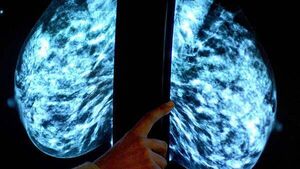

HSE breast cancer screening programme misses targets for past two years

The HSE's national screening service for breast cancer has missed targets for the past two years.

BreastCheck is a free breast screening programme for those aged 50 to 69 years, usually around every two years.